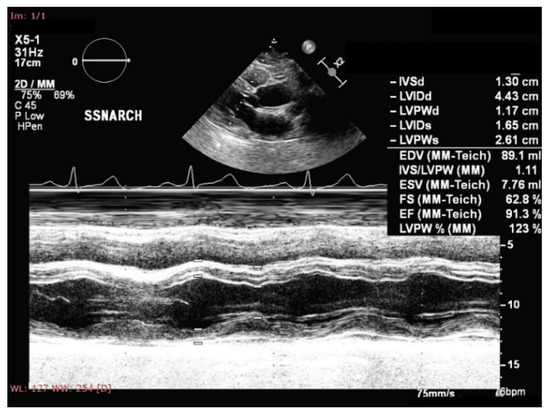

- Abel, E.D.; Litwin, S.E.; Sweeney, G. Cardiac remodeling in obesity. Physiol. Rev. 2008, 88, 389–419. [Google Scholar] [CrossRef]

- Messerli, F.H.; Reisin, E.; Ventura, H.O.; Reisin, E.; Dreslinski, G.R.; Dunn, F.G.; MacPhee, A.A.; Frohlich, E.D. Borderline hypertension and obesity: Two prehypertensive states with elevated cardiac output. Circulation 1982, 66, 55–60. [Google Scholar] [CrossRef]

- Alpert, M.A. Obesity cardiomyopathy: Pathophysiology and evolution of the clinical syndrome. Am. J. Med. Sci. 2001, 321, 225–236. [Google Scholar] [CrossRef]

- Chakko, S.; Allison, M.D.; Mayor, M.; Kessler, K.M.; Materson, B.J.; Myerburg, R.J. Abnormal left ventricular diastolic filling in eccentric left ventricular hypertrophy of obesity. Am. J. Cardiol. 1991, 68, 95–98. [Google Scholar] [CrossRef]

- Tadic, M.; Cuspidi, C. Childhood obesity and cardiac remodeling: From cardiac structure to myocardial mechanics. J. Cardiovasc. Med. 2015, 16, 538–546. [Google Scholar] [CrossRef]

- Esanu, V.; Palii, I.; Mocanu, V.; Vudu, L.; Esanu, V. Left ventricular remodeling patterns in children with metabolic syndrome. One Health Risk Manag. 2020, 1, 41–49. [Google Scholar] [CrossRef]

- Mangner, N.; Scheuermann, K.; Winzer, E.; Wagner, I.; Hoellriegel, R.; Sandri, M.; Zimmer, M.; Mende, M.; Linke, A.; Kiess, W.; et al. Childhood obesity: Impact on cardiac geometry and function. JACC Cardiovasc. Imaging 2014, 7, 1198–1205. [Google Scholar] [CrossRef]